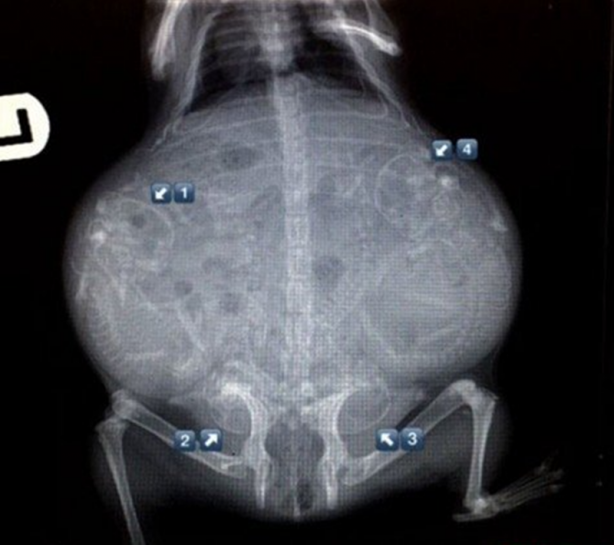

Hamile bir kaplumbağanın röntgen filmi.

Hamile kaplumbağa